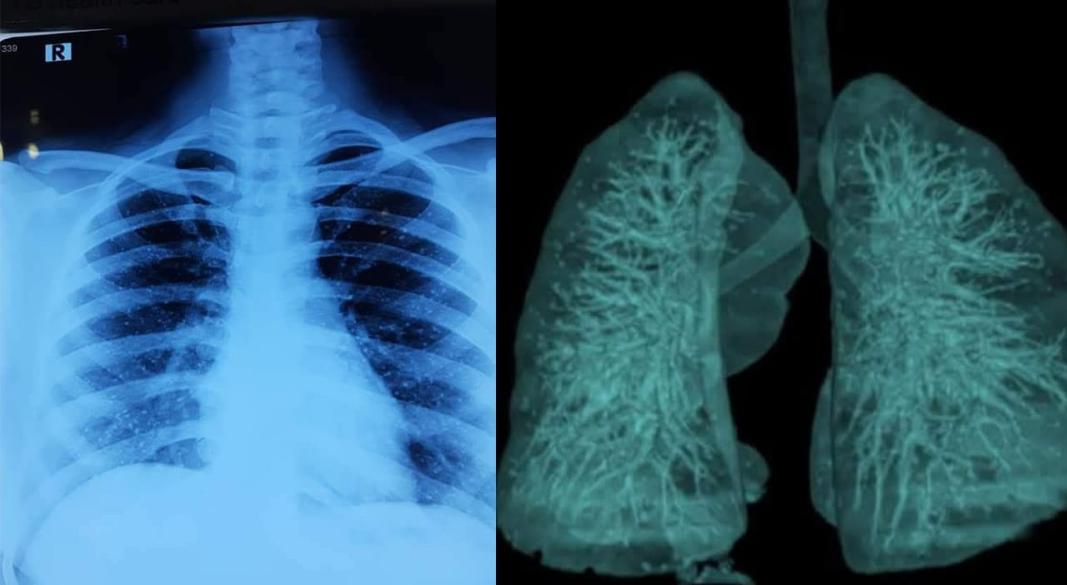

উপসর্গকে গুরুত্ব দিয়ে সতর্কতামূলকভাবে চিকিৎসক একটি চেস্ট এক্স-রে করার পরামর্শ দেন। পরীক্ষার ফলাফল হাতে আসার পর চিকিৎসকরাও বিস্মিত হন। রিপোর্টে দেখা যায়, তার ফুসফুসে অসংখ্য ক্ষুদ্র পাথরের মতো কণা জমে আছে।

চিকিৎসা বিজ্ঞানের ভাষায় এই বিরল রোগটির নাম পালমোনারি এলভিওলার মাইক্রোলিথিয়াসিস (Pulmonary Alveolar Microlithiasis), সংক্ষেপে পিএএম। এ রোগে ফুসফুসের অ্যালভিওলাইয়ের ভেতরে ক্যালসিয়াম ফসফেট জমে ক্ষুদ্র ক্ষুদ্র পাথরসদৃশ গঠন তৈরি হয়।